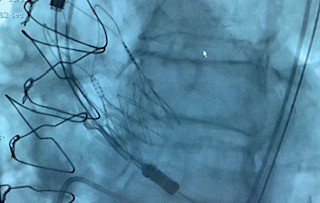

Liberación de una TAVI

Liberación TAV

Liberación TAVI